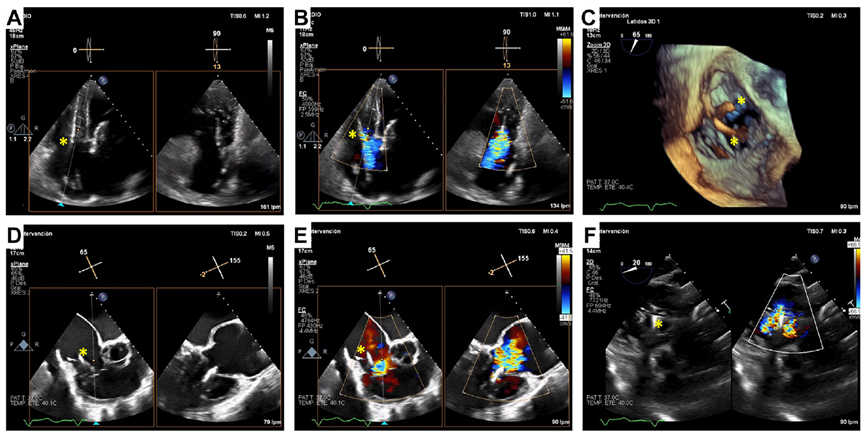

基線經(jīng)胸和經(jīng)食道超聲

術(shù)后經(jīng)食道超聲,僅微量瓣周漏

起搏器/ICD導(dǎo)線引起的TR是三尖瓣反流的主要機(jī)制,這也是三尖瓣介入治療面臨的極大挑戰(zhàn)。既往臨床實(shí)踐已證實(shí)LuX-Valve系列產(chǎn)品在高危三尖瓣反流患者中的安全性和有效性,并且術(shù)后并發(fā)癥發(fā)生率低。LuX-Valve系列產(chǎn)品瓣膜應(yīng)用室間隔“錨定區(qū)域”作為特殊的錨定機(jī)制,保證了瓣膜的穩(wěn)定性。同時(shí),多種尺寸的、較大的自適應(yīng)防漏環(huán)可有效避免瓣周漏的發(fā)生,所以對(duì)于術(shù)前有起搏器/ICD植入史的患者,LuX-Valve系列產(chǎn)品可以最大程度減少由導(dǎo)線引起的三尖瓣殘余反流。本文報(bào)道的病例有兩根導(dǎo)線,其中一根材質(zhì)較厚,位置在瓣膜的中心,手術(shù)的結(jié)果依然很完美。尤其是,LuX-Valve系列產(chǎn)品經(jīng)導(dǎo)管三尖瓣置換系統(tǒng)的調(diào)整和釋放是在緩慢而完全受控的情況下進(jìn)行的,術(shù)者可精確定位和控制導(dǎo)線的位置。隨訪期間,LuX-Valve Plus瓣膜沒(méi)有出現(xiàn)衰敗或血栓的現(xiàn)象,患者生活質(zhì)量也大為改善。